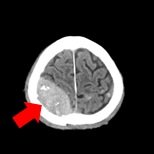

- 頭部

| 頭部領域のCTでは主に脳出血や脳梗塞などの脳の精査、頭部骨折などの骨の精査、耳鼻科領域の精査を目的とした撮影を行います。 | ||

| 単純頭部CT(脳出血) | 骨条件(骨折) | 3D画像(後頭部) |

| 外傷性脳出血+頭蓋骨骨折 | ||